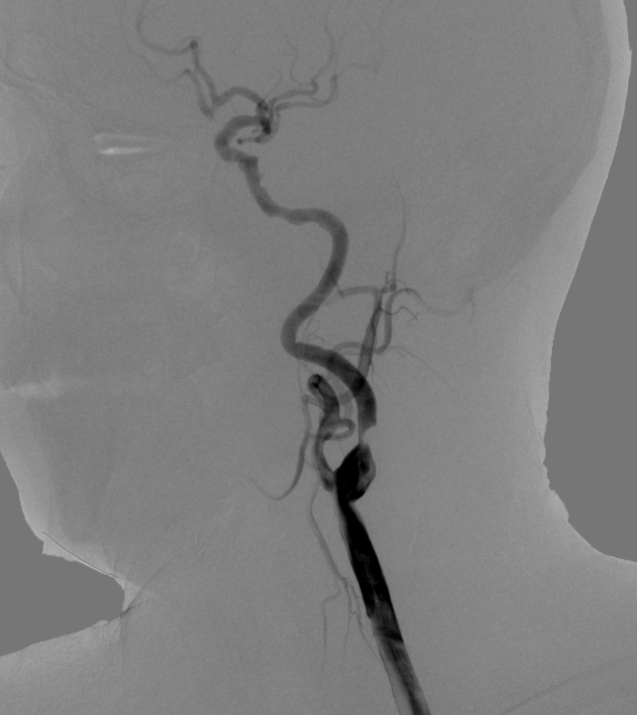

术后造影:

左侧颈内动脉C1段残余狭窄约10%,远端血管显影良好,前向血流mTICI 3级,未见远端血管栓塞及造影剂外渗。